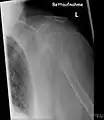

- Vues de fractures pathologiques

Fracture pathologique de l'humérus sur une métastase de carcinome du rein

Fracture pathologique du bras gauche sur une métastase osseuse de cancer du sein

Pour le diagnostic initial, la radio X classique a une importance centrale. L'indication pour des projections sur deux plans est toujours donnée en cas de soupçon de tumeur osseuse[87]. Les métastases ostéolytiques sont caractérisées par une perte de densité osseuse. Ceci se reconnaît sur la radio par un noircissement plus élevé, en raison de la plus grande transparence aux rayons X. Inversement, les métastases ostéocondensantes présentent à cause de la plus grande densité osseuse un noircissement inférieur. Les métastases ostéolytiques sur la colonne vertébrale sont nettement plus difficiles à reconnaître : seulement quand environ 50 % de la densité totale de l'os a disparu[87].